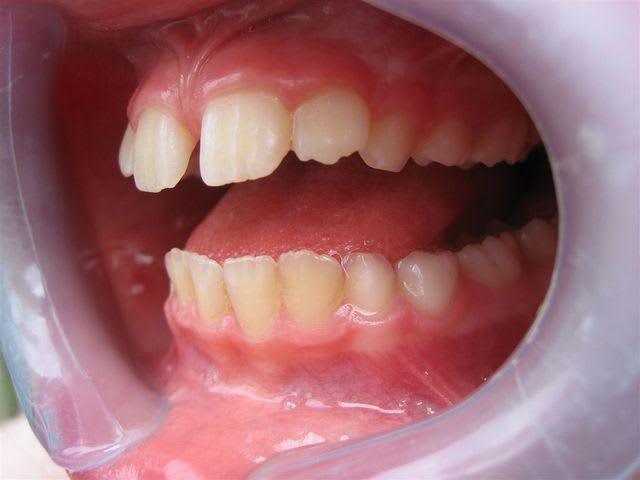

... ma gamine, bientôt 9 ans.

Père CD ... traitement d'ortho.

Mère CD ... traitement d'ortho.

Les conseils sont les bienvenus.

... je vous rassure, le reste de la gamine est lui plutôt réussit.

... pas de rapport avec Tchernobyl ... enfin j'espère!

C’est un cas simple ou il faut juste stimuler un peu la croissance et reformer les arcades.

C’est le type même du traitement d’interception en denture mixte.

Pas de panique, petite DDM, bonne classe 2 sq,un peu de supracclusion ---> la laisser grandir un peu, et la confier à un ODF pour un peu de fonctionnelle et un alignement.

... elle est en classe I, avec une grosse supra.

TT "fonctionnel" prévu dans qqs semaines.